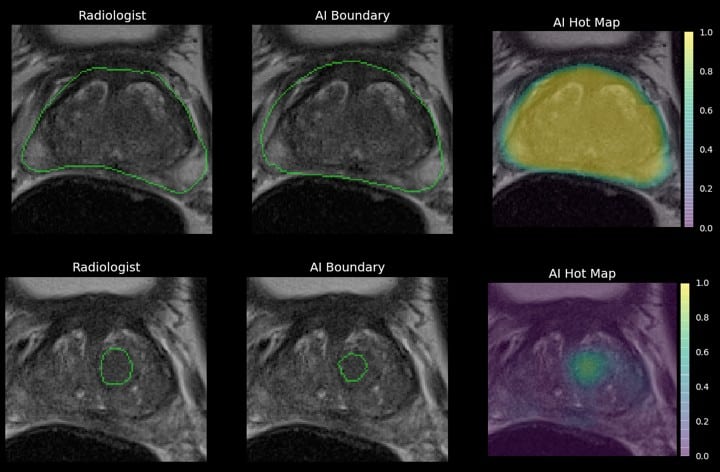

The presentation by Emi Gal of Ezra was as engaging. After a lighthearted intro, he quickly launched into a series of statistical data, showing how devasting cancer can be if not caught early. Yet, most healthcare system worldwide still do not offer a comprehensive easy pre-screening that could save millions of lives, mostly because of the complexity of the procedures. This is what Emi is solving, with his company Ezra. Using an MRI coupled with Artificial Intelligence, Ezra can run a full pre-diagnostic on over 11 types of cancers in one go, allowing doctors to quickly spot potential issues.